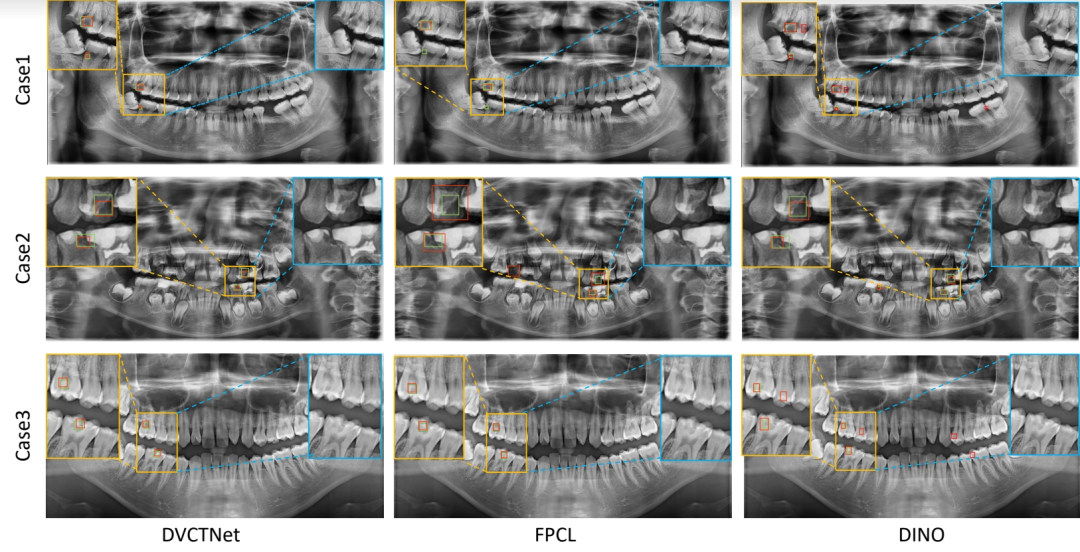

龋病是最常见的口腔疾病之一, 从口腔全景 X 光片中的准确检测龋病对防止病变恶化具有重要意义。由于龋病在全景片上细微的对比度差异和多样的形态特征,现有检测方法往往难以达到理想精度。崔智铭教授课题组硕士研究生罗涛等提出了一个基于基础模型的双视角协同训练框架,以实现高精度的龋病检测。该研究受临床工作流程启发,设计了一种名为 DVCTNet 的新型双视图协同训练网络。实验结果表明,DVCTNet 优于目前最先进方法,展现出卓越的性能优势,进一步验证了其在临床场景中应用的可行性与可靠性, 为其在实际口腔诊疗中的推广应用奠定了坚实基础。

论文题目:Adapting Foundation Model for Dental Caries Detection with Dual-View Co-Training